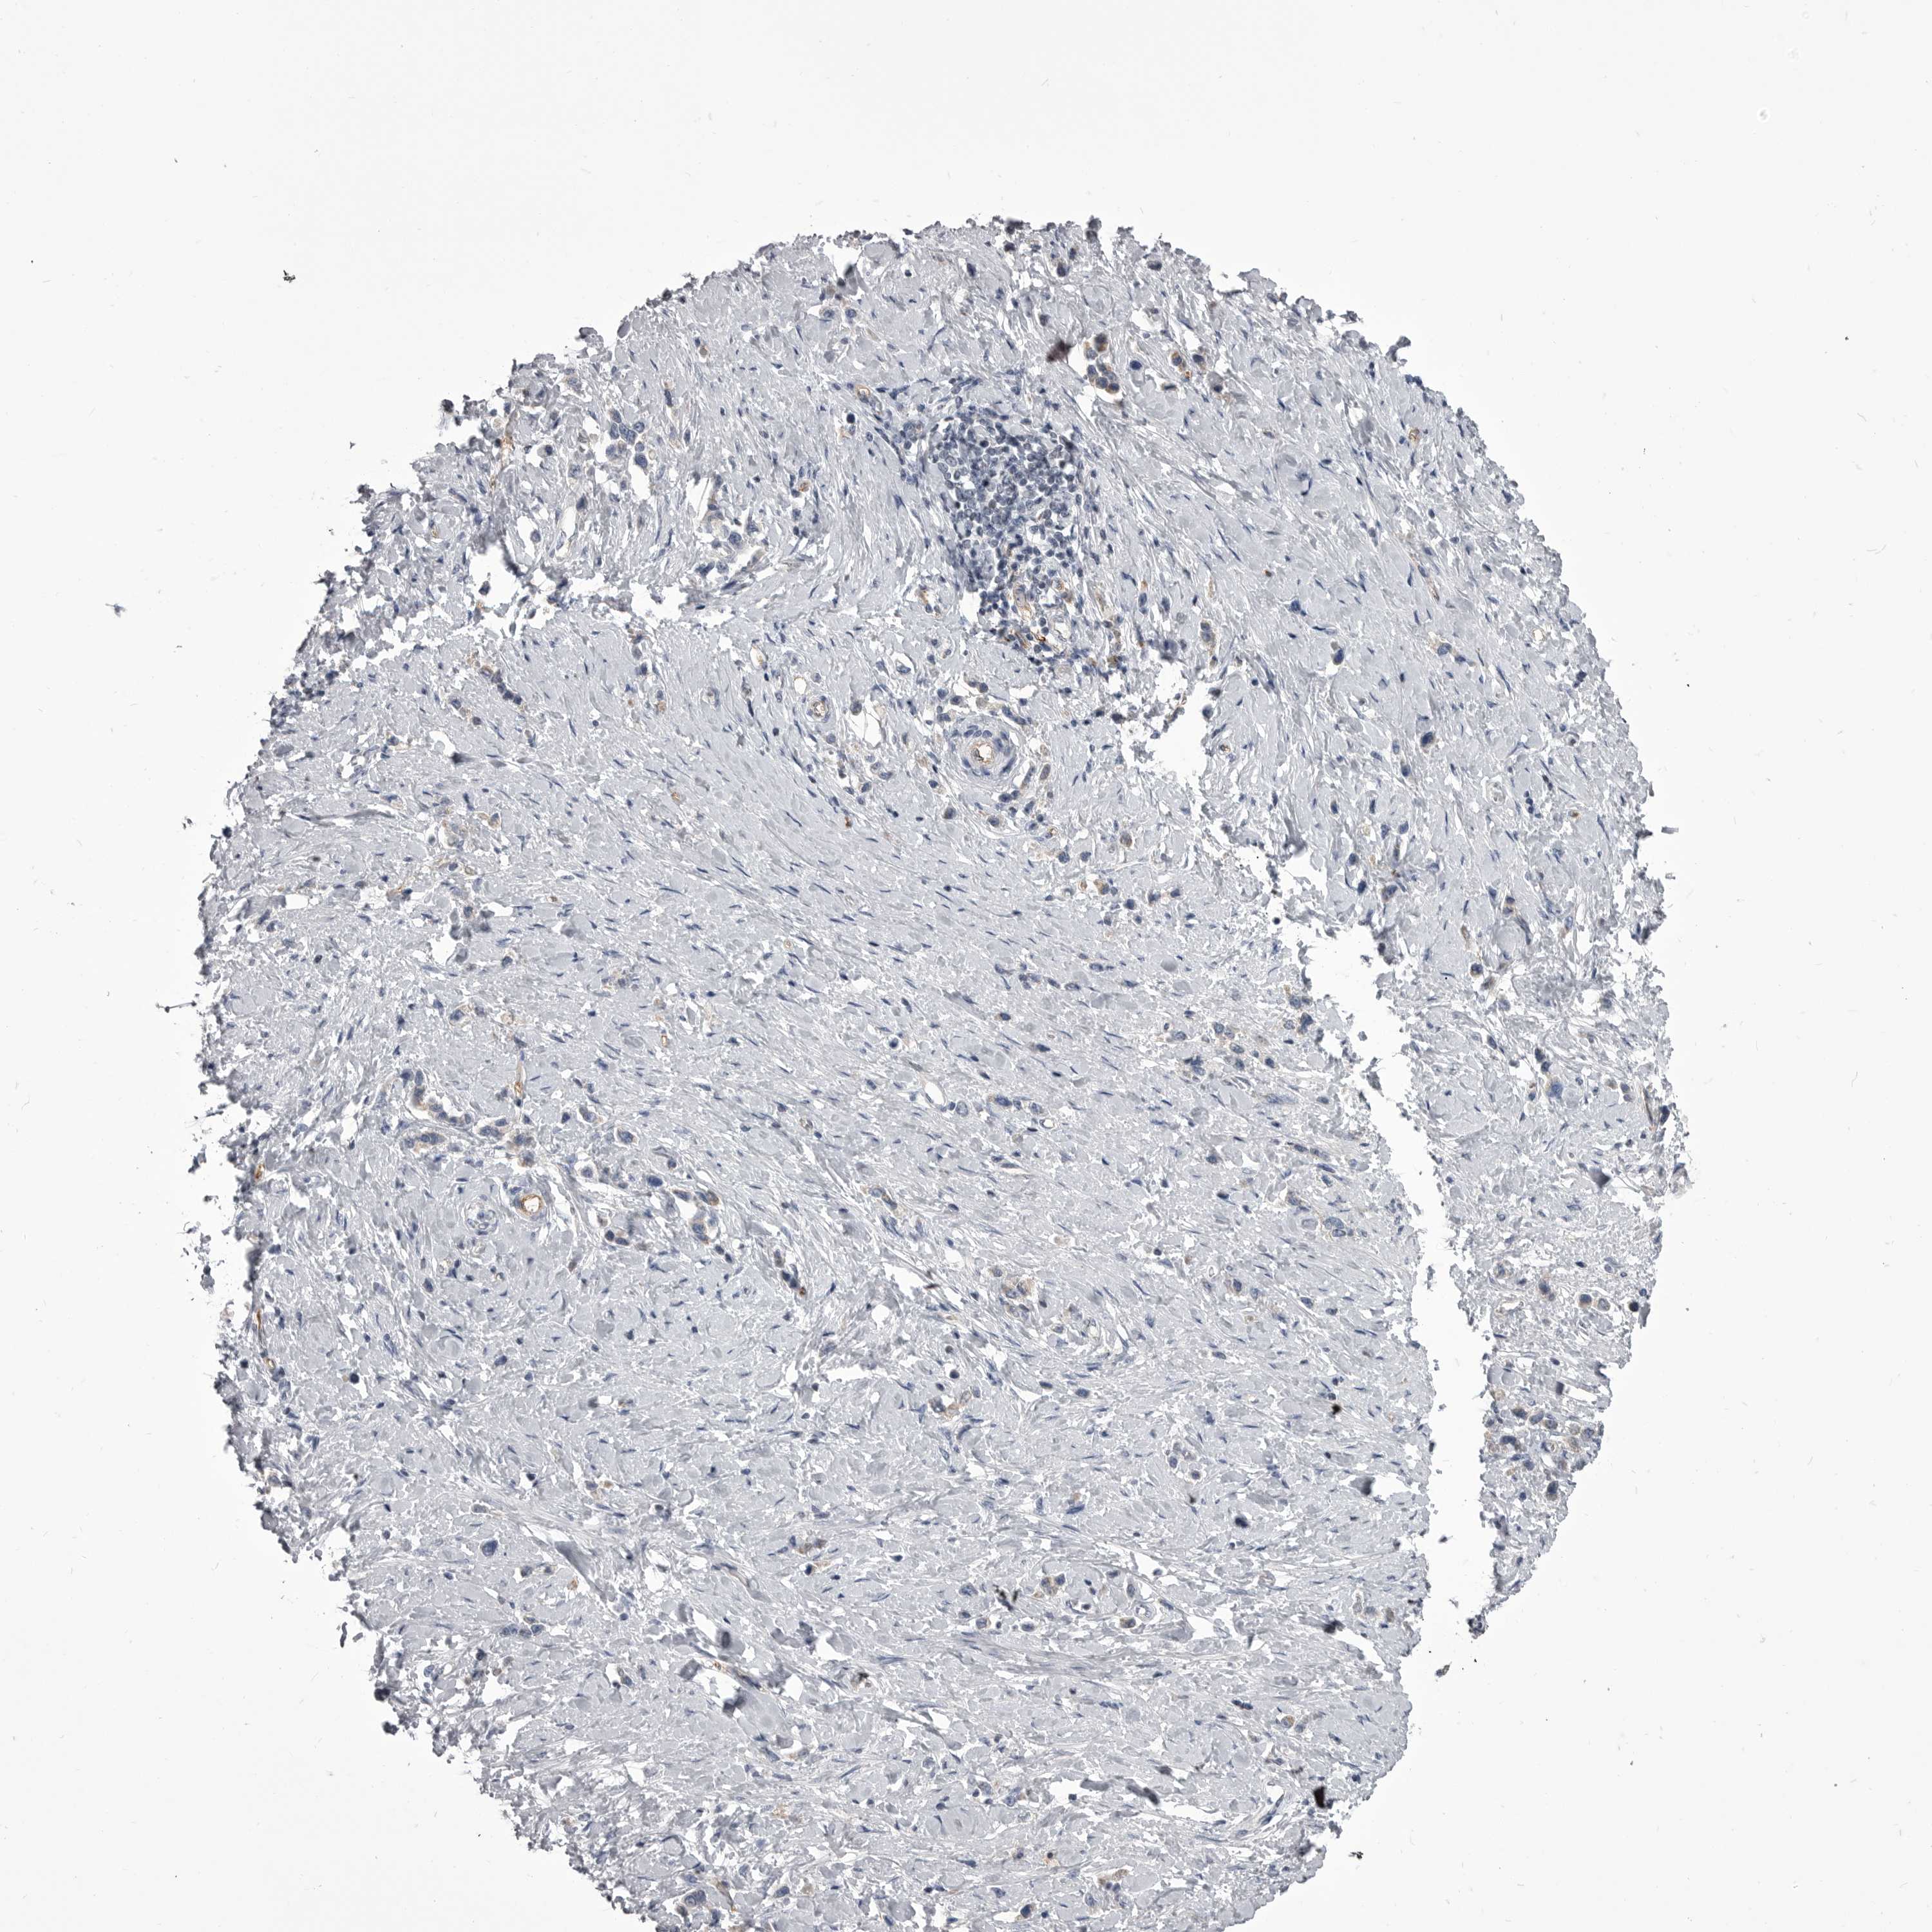

STOMACH CANCER - Protein expressioni

A mouse-over function shows sample information and annotation data. Click on an image to view it in a full screen mode. Samples can be filtered based on level of antibody staining by selecting one or several of the following categories: high, medium, low and not detected. The assay and annotation is described here.

Note that samples used for immunohistochemistry by the Human Protein Atlas do not correspond to samples in the TCGA dataset.

Antibody stainingi

Antibody staining in the annotated cell types in the current human tissue is reported as not detected, low, medium, or high, based on conventional immunohistochemistry profiling in selected tissues. This score is based on the combination of the staining intensity and fraction of stained cells.

Each image is clickable and will lead to virtual microscopy that enables deeper exploration of all samples and also displays staining intensity scores, fraction scores and subcellular localization as well as patient and tissue information for each sample.

Antibody HPA026562

Antibody HPA028260

Staining

High

Medium

Low

Not detected

Intensity

Strong

Moderate

Weak

Negative

Quantity

>75%

75%-25%

<25%

None

Location

Nuclear

Cytoplasmic/membranous

Cytoplasmic/membranous,nuclear

Adenocarcinoma, NOS